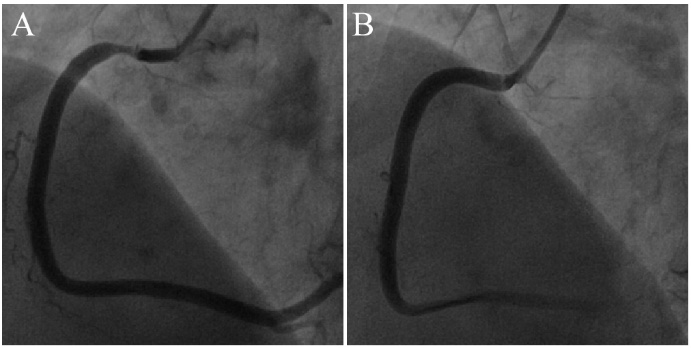

因此,一旦造影发现支架两端或非支架部位血管细小,凸显出支架“突兀过大”,极有可能是冠脉痉挛(图7-8)。

图7 右冠中段支架突兀提示冠脉痉挛。

整个右冠血管弥漫变细,中段支架“突兀和过大”(A),冠脉内注射硝酸甘油后血管明显增粗(B)!箭头所示为支架两端。

图8 前降支近段支架突兀提示冠脉痉挛。

前降支近中段支架基本通畅,中远段血管弥漫性均匀变细,管壁光滑。凸显出支架“突兀和过大”(A),冠脉内注射硝酸甘油后支架外狭窄消失,支架大小合适(B)!箭头所示为支架两端。